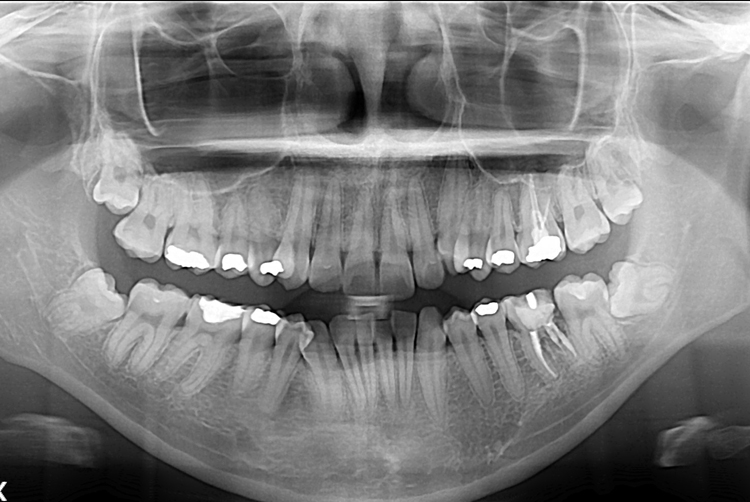

[임플란트] 어금니 임플란트

치료전 : 2017-04-10

세종치과는 많은 환자와 다양한 케이스를 바탕으로

항상 편안한 임플란트 수술을 제공하고자 노력하고,

오래동안 튼튼히 쓸 수 있는 임플란트 수술을 가장 큰 목표로 삼고 있습니다.